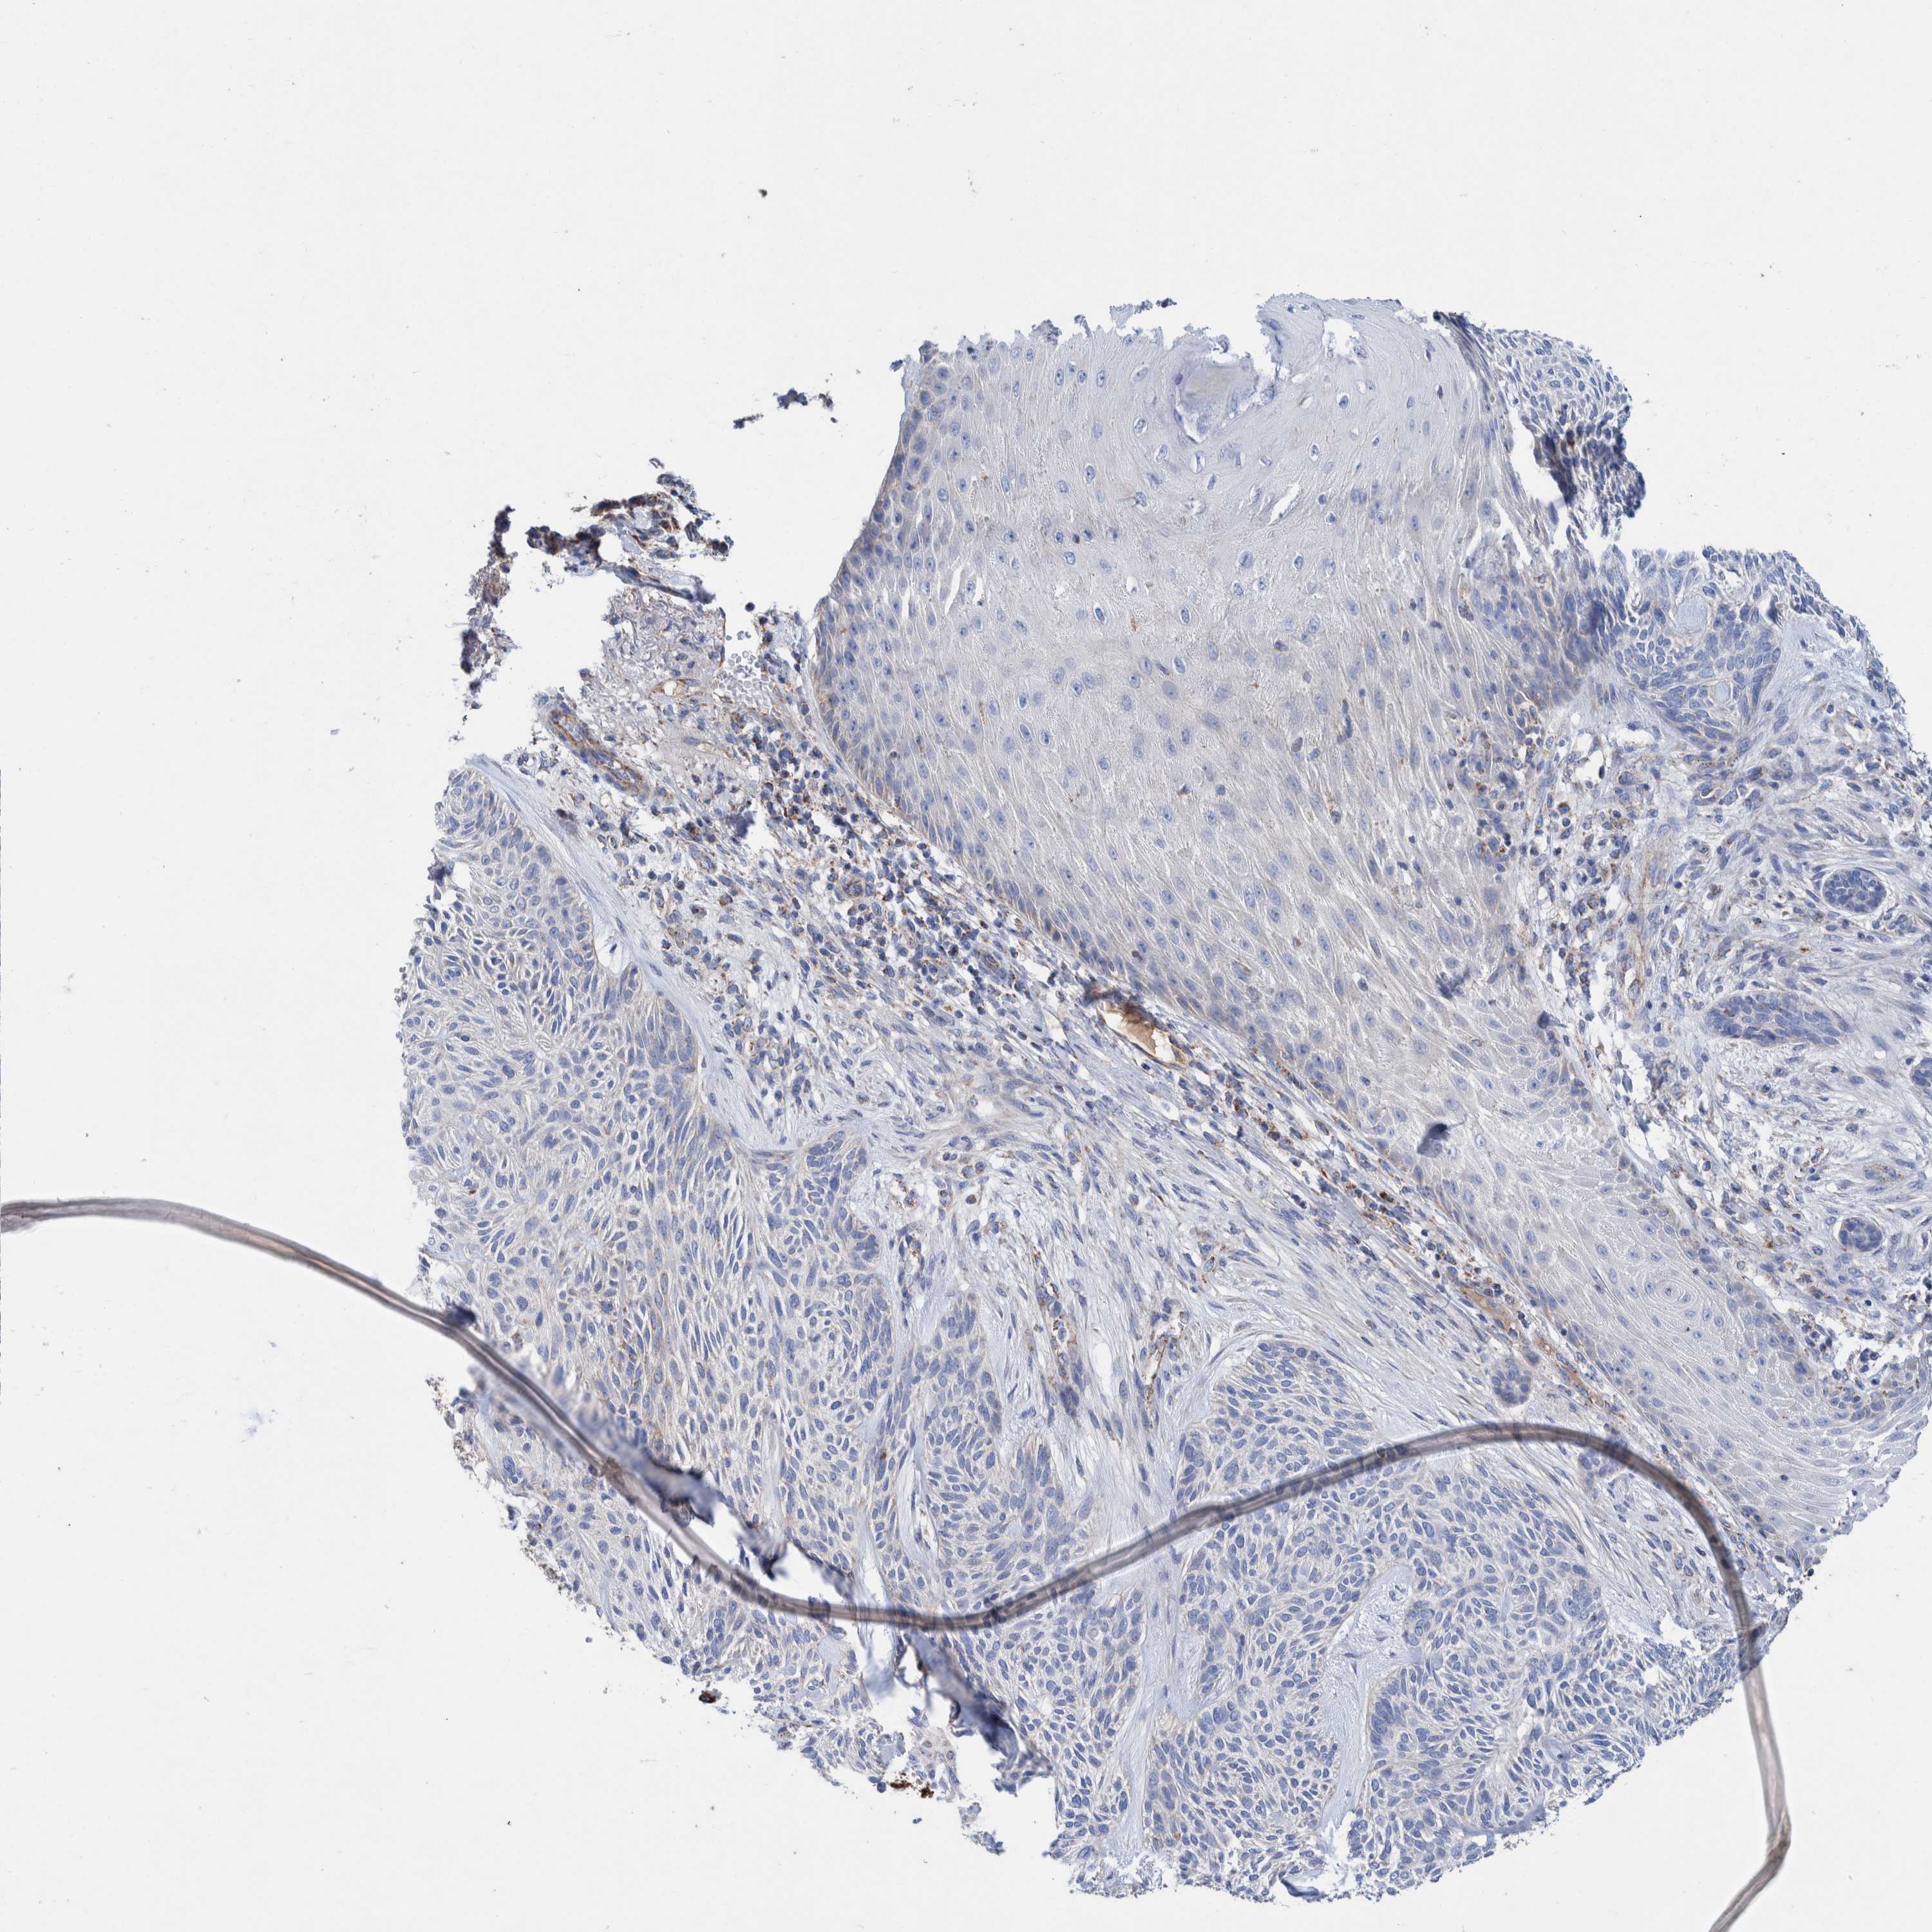

CANCER SKIN CANCER Show tissue menu

Basal cell and squamous cell cancer

SKIN CANCER - Protein expressioni

A mouse-over function shows sample information and annotation data. Click on an image to view it in a full screen mode. Samples can be filtered based on level of antibody staining by selecting one or several of the following categories: high, medium, low and not detected. The assay and annotation is described here.

Each image is clickable and will lead to virtual microscopy that enables deeper exploration of all samples and also displays staining intensity scores, fraction scores and subcellular localization as well as patient and tissue information for each sample.

Antibody HPA023160

Antibody HPA023162

Antibody HPA023238

Basal cell carcinoma

Squamous cell carcinoma, NOS

Squamous cell carcinoma, metastatic, NOS